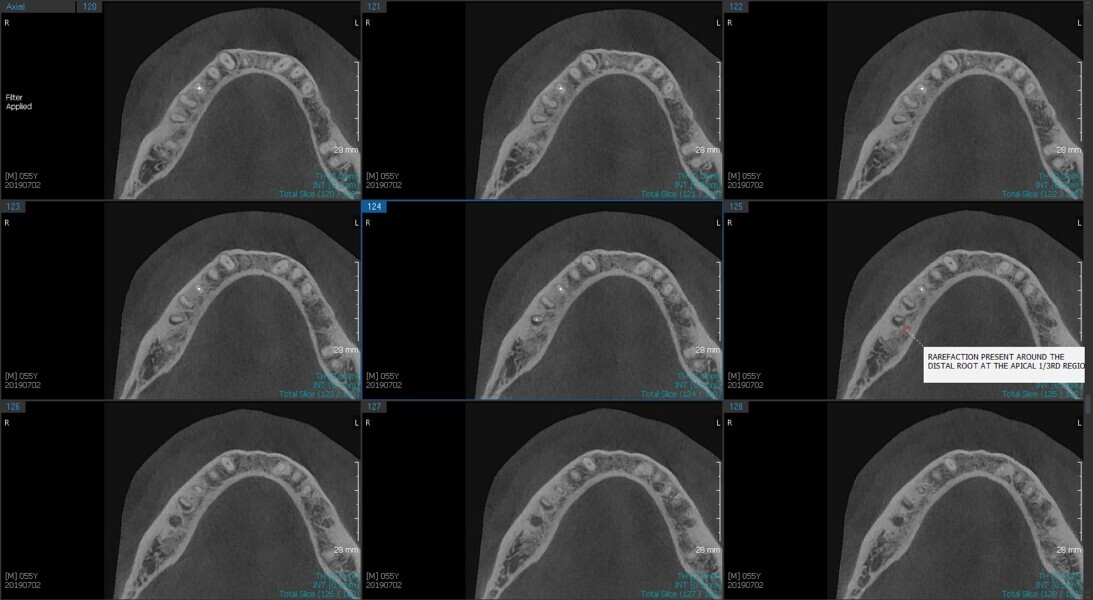

Fig.2a: Pre-op CBCT images of tooth #46: No obturation material in the distal and mesiobuccal canal (a); scanty obturation of the canals and breach of the floor of the pulp chamber, no obturation beyond a few millimetres down the orifice (b & c); radiolucency in the furcation area and periapical region of both roots (d -g).

Fig.2b: Pre-op CBCT images of tooth #46: No obturation material in the distal and mesiobuccal canal (a); scanty obturation of the canals and breach of the floor of the pulp chamber, no obturation beyond a few millimetres down the orifice (b & c); radiolucency in the furcation area and periapical region of both roots (d -g).

Fig.2c: Pre-op CBCT images of tooth #46: No obturation material in the distal and mesiobuccal canal (a); scanty obturation of the canals and breach of the floor of the pulp chamber, no obturation beyond a few millimetres down the orifice (b & c); radiolucency in the furcation area and periapical region of both roots (d -g).

Fig.2d: Pre-op CBCT images of tooth #46: No obturation material in the distal and mesiobuccal canal (a); scanty obturation of the canals and breach of the floor of the pulp chamber, no obturation beyond a few millimetres down the orifice (b & c); radiolucency in the furcation area and periapical region of both roots (d -g).

Fig.2e: Pre-op CBCT images of tooth #46: No obturation material in the distal and mesiobuccal canal (a); scanty obturation of the canals and breach of the floor of the pulp chamber, no obturation beyond a few millimetres down the orifice (b & c); radiolucency in the furcation area and periapical region of both roots (d -g).

Fig.2f: Pre-op CBCT images of tooth #46: No obturation material in the distal and mesiobuccal canal (a); scanty obturation of the canals and breach of the floor of the pulp chamber, no obturation beyond a few millimetres down the orifice (b & c); radiolucency in the furcation area and periapical region of both roots (d -g).

Fig.2g: Pre-op CBCT images of tooth #46: No obturation material in the distal and mesiobuccal canal (a); scanty obturation of the canals and breach of the floor of the pulp chamber, no obturation beyond a few millimetres down the orifice (b & c); radiolucency in the furcation area and periapical region of both roots (d -g).